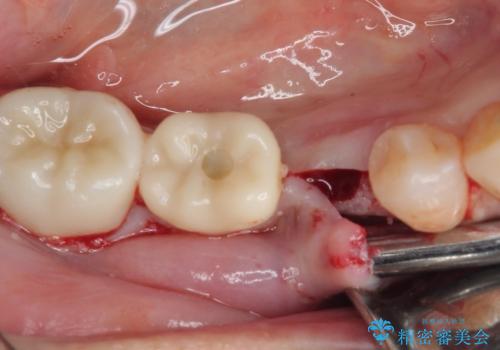

土台の材料を外して顕微鏡下で確認したところ、歯根にまで及ぶ破折が認められたため、インプラント治療を行うこととしました。

他にも銀歯や欠損となっている歯に対しての治療も希望されたため、補綴治療を行うこととしました。